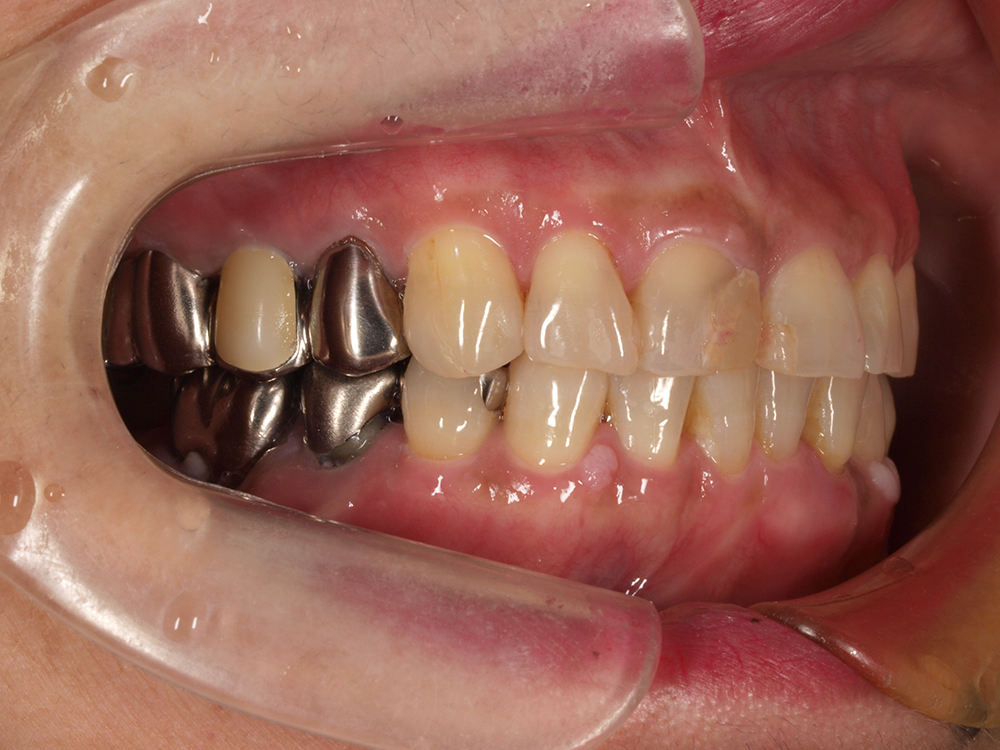

55歳 男性

- 主訴

- 前歯でしか咬めなく、食事を採るのに非常に困難で辛い

- 処置内容

- 上顎6本、下顎3本

- 治療費用

- 上顎:約230万(税込)下顎:約120万(税込)

- 治療期間

- 上顎:1年(仮歯まで8か月)下顎:8か月(仮歯まで5か月)

- リスク

- 上部構造物、仮歯の破折、術後の腫れ(3日)、人工歯根脱落リスクがあります